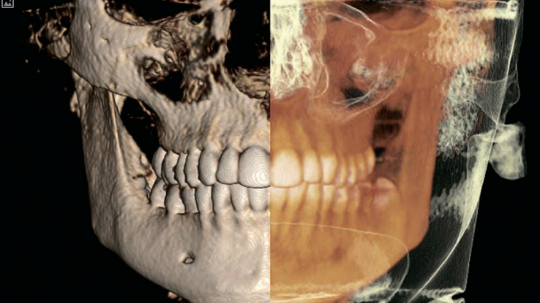

Один из самых информативных рентгеновских способов качественной диагностики заболеваний челюстно-лицевого аппарата. В результате КЛКТ врач получает 3D изображение исследуемого участка. Использование КЛКТ в стоматологии, лицевой хирургии позволяет обнаружить отклонения, поставить точный диагноз и назначить необходимое лечение

•  3D сканирование на 360 градусов охватывает

оральные и лицевые области

• Стандартное изображение челюсти размерами 8

см в диаметре и высотой 8 см используется для

планирования имплантаций, эндодонтического

лечения и хирургических вмешательств